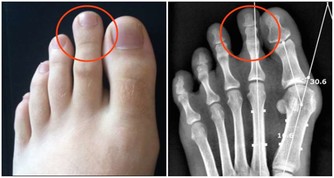

什麼人不適合吃香蕉? 1:體質偏虛寒者 香蕉性寒體質偏虛寒者最好避之則吉,像胃寒、虛寒、腎炎、也不要吃香蕉,以上幾種病人如果吃香蕉也不利於身體的健康。還有點懷孕期腳腫的患者,也最好是不要吃香蕉。 2:空腹的人 香蕉是可以促進胃腸道蠕動的,如果空腹吃就會造成腸胃的提前工作,長期空腹吃香蕉也不利於身體的健康。為什麼不能空腹吃香蕉呢,因為空腹時腸胃中幾乎沒有可提供消化的食物,在空腹時吃香蕉就會加快腸胃的運動,促進血液的循環,增強心臟的負荷,容易導致心肌梗塞。 3:關節炎患和糖尿病患者 香蕉的含糖量是比較高的,會使血液循環減慢,代謝物堆積,如果關節炎和糖尿病患者不應該吃香蕉,否則會加重病情。 4:腎炎患者 腎炎患者也是不可以吃香蕉的,因為香蕉中含有大量的鉀、鎂元素,腎炎患者的派濾功能比較差,香蕉會使血液中的鈣鉀鎂比例失調,進而促進腎病的加重,所以腎病寒者最好是不要吃香蕉。